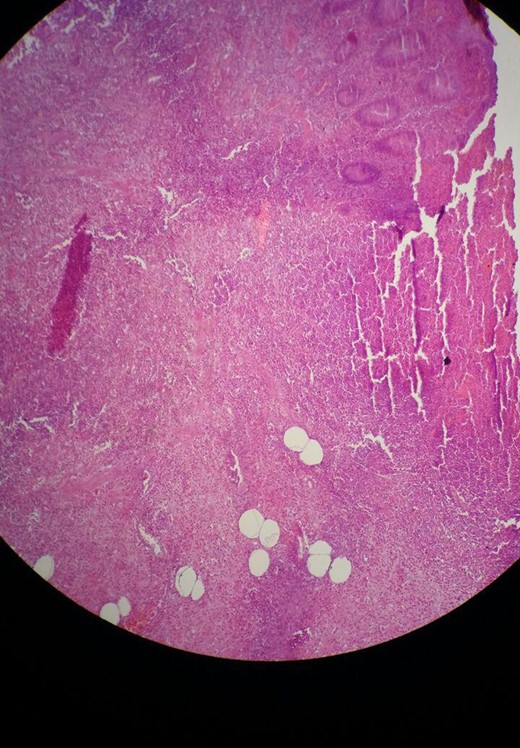

A 30-year-old female presented to the emergency department complaining of abdominal pain. The pain started 48 h ago diffusely in the umbilical region and subsequently migrated to the right iliac fossa. She had associated nausea, vomiting and loss of appetite. There was no alteration in bowel habits. The patient was otherwise healthy and has not undergone any previous abdominal or pelvic surgeries. On physical examination the patient was febrile (39°C) and tachycardic. Examination of the abdomen revealed localized tenderness as well as rebound tenderness at the McBurney point in the right iliac fossa. Laboratory findings showed severe leukocytosis (22 000/ul) with a left shift (neutrophils 88%), and increased C reactive protein (100 mg/dl). Urinalysis did not reveal any specific findings and urine pregnancy test was negative. Abdominal ultrasonography was performed and revealed an appendiceal shield, free fluid, and abscess formation in the right iliac fossa. A definite diagnosis of acute appendicitis was made based on Alvarado score of (10) and a decision was made to perform an open appendectomy via a Rocky Davis incision. Intraoperative findings showed a small quantity of free fluid in the abdomen and two appendices lying on either side of the ileocecal valve, one of them was swollen and erythematous (Fig. 1). The surgeon resected the two appendices. Histopathological examination confirmed the diagnosis of appendiceal duplication. The first specimen showed an inflamed appendix with lymphoid hyperplasia, thickened muscularis and prominent neutrophilic infiltration compatible with acute appendicitis (Fig. 2). The second specimen showed a normal appendix without serosal inflammation, or neutrophilic infiltrate in the muscularis propria (Fig. 3). The tip was present without any lesions. The patient had a full recovery without postoperative complications and was discharged on the third postoperative day.

Microscopic view of the second specimen with a nearly normal appendix. Sections show a thin walled appendix lined by a colonic type glandular epithelium.